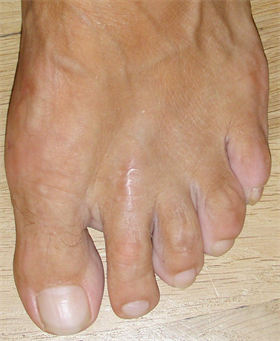

Figure 10. Patient Nr 2. Clinical appearance before the operation.

Figure 11. (a) Patient Nr. 2. Result after 7 years; (b) Medic ballerina for undisturbed walking with bulky dressing or swellings